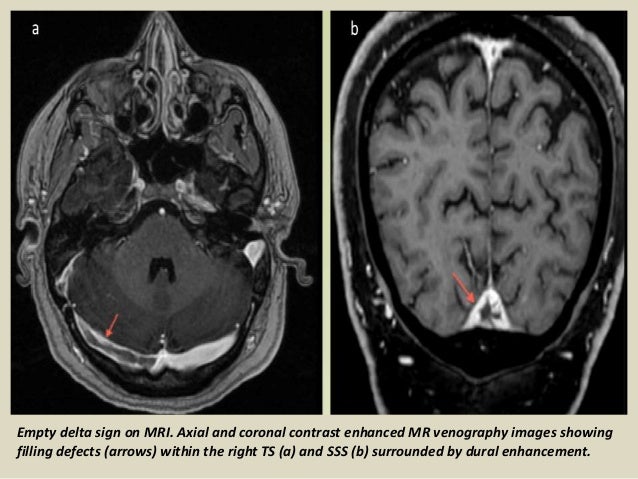

Venous phase image (c) shows thrombosis of superior sagittal sinus with numerous dilated collateral venous channels.

Cerebral venous sinus thrombosis created by paul young 22/11/07. Cerebral venous and sinus thrombosis (cvst) is a rare disease responsible for less than 1% from the total of avc causes (bajenaru, 2010). Cerebral venous sinus thrombosis is an uncommon cause of stroke presenting with varied presentation patterns. Die thrombosen der intrakraniellen venen und sinus, stuttgart, 1965; This prevents blood from draining out of the brain. Acute symptomatic seizures in cerebral venous thrombosis. This condition may also be called cerebral sinovenous thrombosis. Chronic thrombosis of cerebral venous sinuses. Cerebral venous thrombosis (cvt) is a rare form of cerebrovascular disease in which thrombus forms in the dural sinuses and cortical cerebral veins. Saudi j med med sci 2019;7:135‑6. 1 three subtypes of cerebral venous and sinus thrombosis (cvst). What causes cerebral venous sinus thrombosis? Venous phase image (c) shows thrombosis of superior sagittal sinus with numerous dilated collateral venous channels.